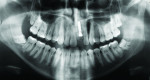

After 11 years, at 17 years of age, the patient expressed interest in a definitive treatment plan to address the associated increased mobility and short clinical crown length of the left maxillary incisor. The clinical examination revealed compromised gingival architecture in disharmony with adjacent teeth, an incisal edge position apical to the incisal edge position of the maxillary right central incisor, and a reduced anteroposterior ridge (Figure 1). The radiographic examination revealed severe root replacement resorption (Figure 2). Treatment options discussed included extraction of the left maxillary incisor followed by placement of a removable and fixed-tooth or implant-supported restoration. A staged treatment approach to maximize esthetic and functional treatment outcome with surgical soft- and hard-tissue augmentation procedures was also discussed with patient and parent but was declined. The patient elected to proceed with extraction of the unsalvageable left maxillary incisor and placement of an immediate provisional removable partial denture.